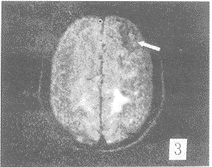

在FLAIR序列所发现81个病灶中,FSET2序列能显示的有66个,FSET2序列对病变显示率 为81.4%。FSET2序列未显示的15个病灶均位于侧脑室下、脑室旁及脑灰质区(图1,2) 。位 于脑室下的病灶,T2像未能显示。而位于基底节区,脑白质区的病灶,FLAIR及FSET2序列都 能显示。T2加权像上,所有病灶均为高信号。但在FLAIR序列,有2个病灶为低信号,1例出 血,出血灶的低信号部份T2像未能显示。另1例是T2加权像没能显示的血管畸形远端侧枝 循环(图3,4),此例为左侧颈内动脉畸形,左顶叶侧枝循环,T2像未能显示。在T2像上没能 显示而FLAIR像显示的15个病灶中,有10例为脑梗塞、脱髓鞘病变和皮层下动脉硬化性脑病 , 病灶位于脑灰质,受脑脊液影响T2像未能显示。2例为转移瘤(图5,6),肿瘤位于脑灰质,T 2像仅见水肿影。2例为脑炎、脑膜炎(图7,8),在T2像上病灶完全被脑沟中的脑脊液所掩盖 。

图3 FLAIR像左侧颈内动脉畸形,伴左顶叶远端侧枝循环,为树枝 状低信号。FSET2像(图4)左顶叶相同部位未见树枝状低信号